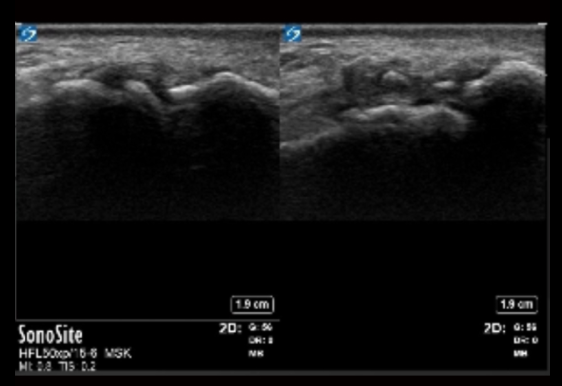

手部 MCP 关节及病变图像